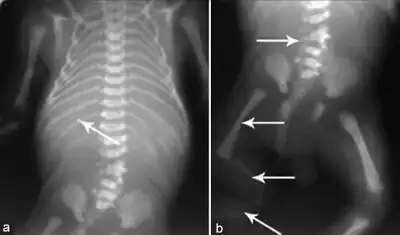

a) Hypoplastic mandible b)hypoplasia of right lower limb c) dilated urinary bladder asterisk and bilateral hydroureters arrowheads